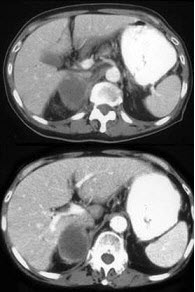

男,75岁,右侧胸痛伴咯血3月余,胸部CT提示右侧中央型肺癌,请结合图像,作出诊断( )

A:右侧肾上腺囊肿

B:右侧肾上腺转移瘤

C:右侧肾上腺腺瘤

D:右侧肾上腺癌

E:右侧肾上腺嗜铬细胞瘤